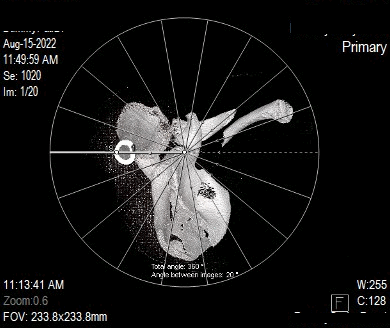

Series of Images Send to SyngoVia

1. Shoulder 0.6 B31s

Series of Images Send From SyngoVia to PACS

1. Radial ranges of shoulder

Series of Images Send to PACS

1. Topogram

2. Shoulder 5.0 B60s

3. Shoulder 0.6 B31s

4. Shoulder 0.6 B60s

5. Patient Protocol